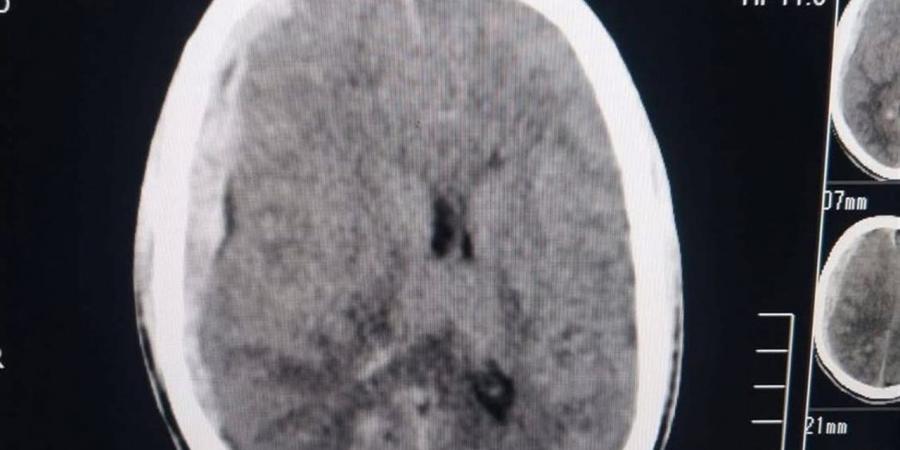

وتم التعامل مع الحالة بشكل فوري وفق بروتوكولات الطوارئ المتقدمة، حيث جرى تأمين مجرى الهواء عن طريق تركيب أنبوبة حنجرية، ووضع المريض على جهاز التنفس الصناعي. كما أظهرت الأشعة المقطعية على المخ وجود نزيف تحت الجافية (SDH) ونزيف تحت العنكبوتية (SAH).

وتم حجز المريض بوحدة عناية الطوارئ والحالات الحرجة المركزة، حيث خضع للعلاج التحفظي مع متابعة دقيقة لمستوى الوعي والعلامات العصبية. وأكدت إعادة الأشعة المقطعية استقرار الحالة وعدم زيادة حجم النزيف، مما دعم الاستمرار في الخطة العلاجية.

وبفضل المتابعة الدقيقة والرعاية المتكاملة، تحسنت الحالة بشكل ملحوظ حتى وصلت إلى درجة الوعي: 15/15 معدل التنفس: 18/دقيقة ونسبة الأكسجين: 99% على هواء الغرفة، كما أظهرت الأشعة تحسنًا واضحًا وانخفاضًا في حجم النزيف.